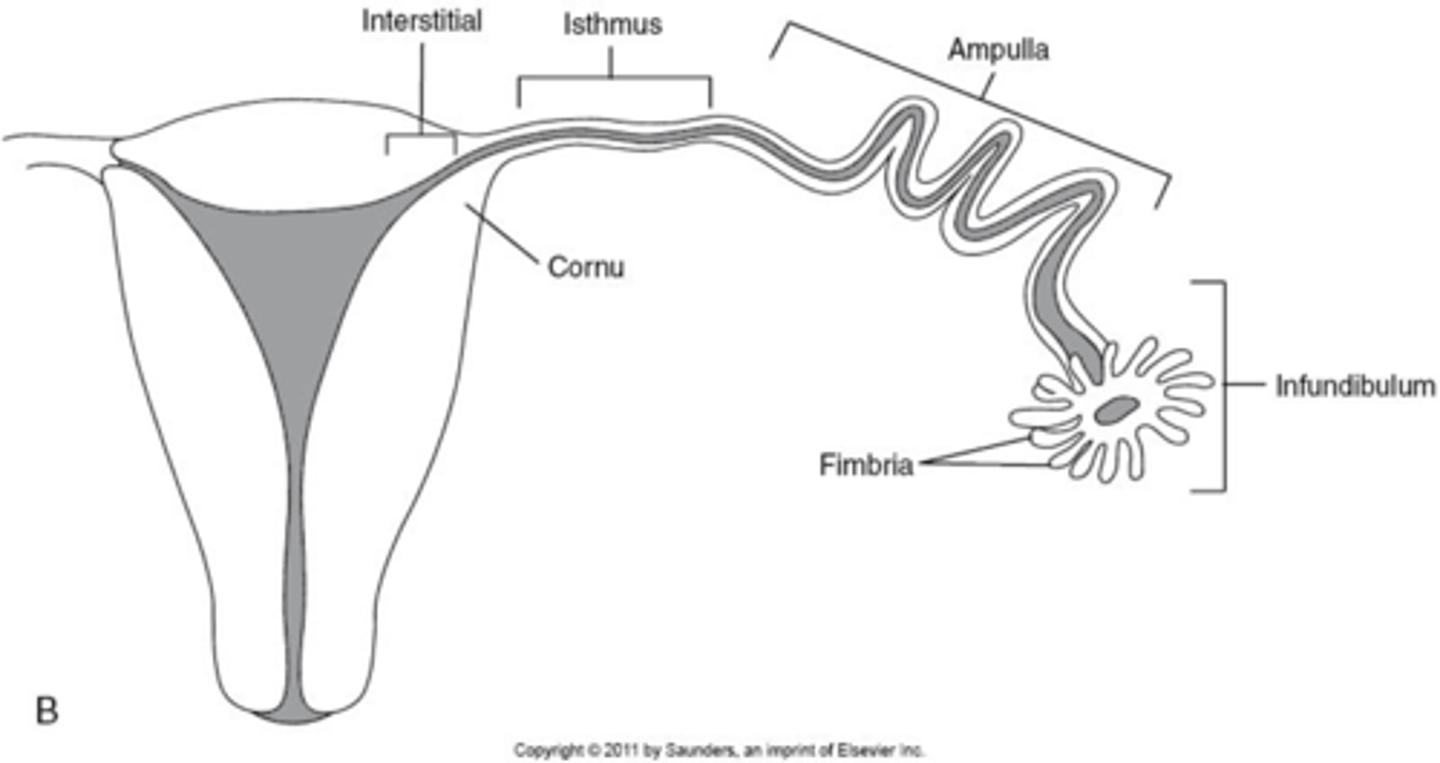

What are fallopian tubes also called?

uterine tubes

oviducts

The fallopian tubes are ____, muscular tubes

coiled

The fallopian tubes emerge from the ____ margins of the uterine cornua

superolateral

The fallopian tubes direct mature ___ to the ___ through ___

ovum; uterus; peristalsis

The fallopian tubes are ___ long with a diameter of ___

10 to 12 cm

1 to 4 mm

What are the 4 segments of the fallopian tubes?

1. interstitial

2. isthmus

3. ampulla

4. infundibulum

What part of the fallopian tube is the widest segment where fertilization occurs?

ampulla

What part of the fallopian tube is the most dangerous to have an ectopic pregnancy?

interstitial bc most vascular